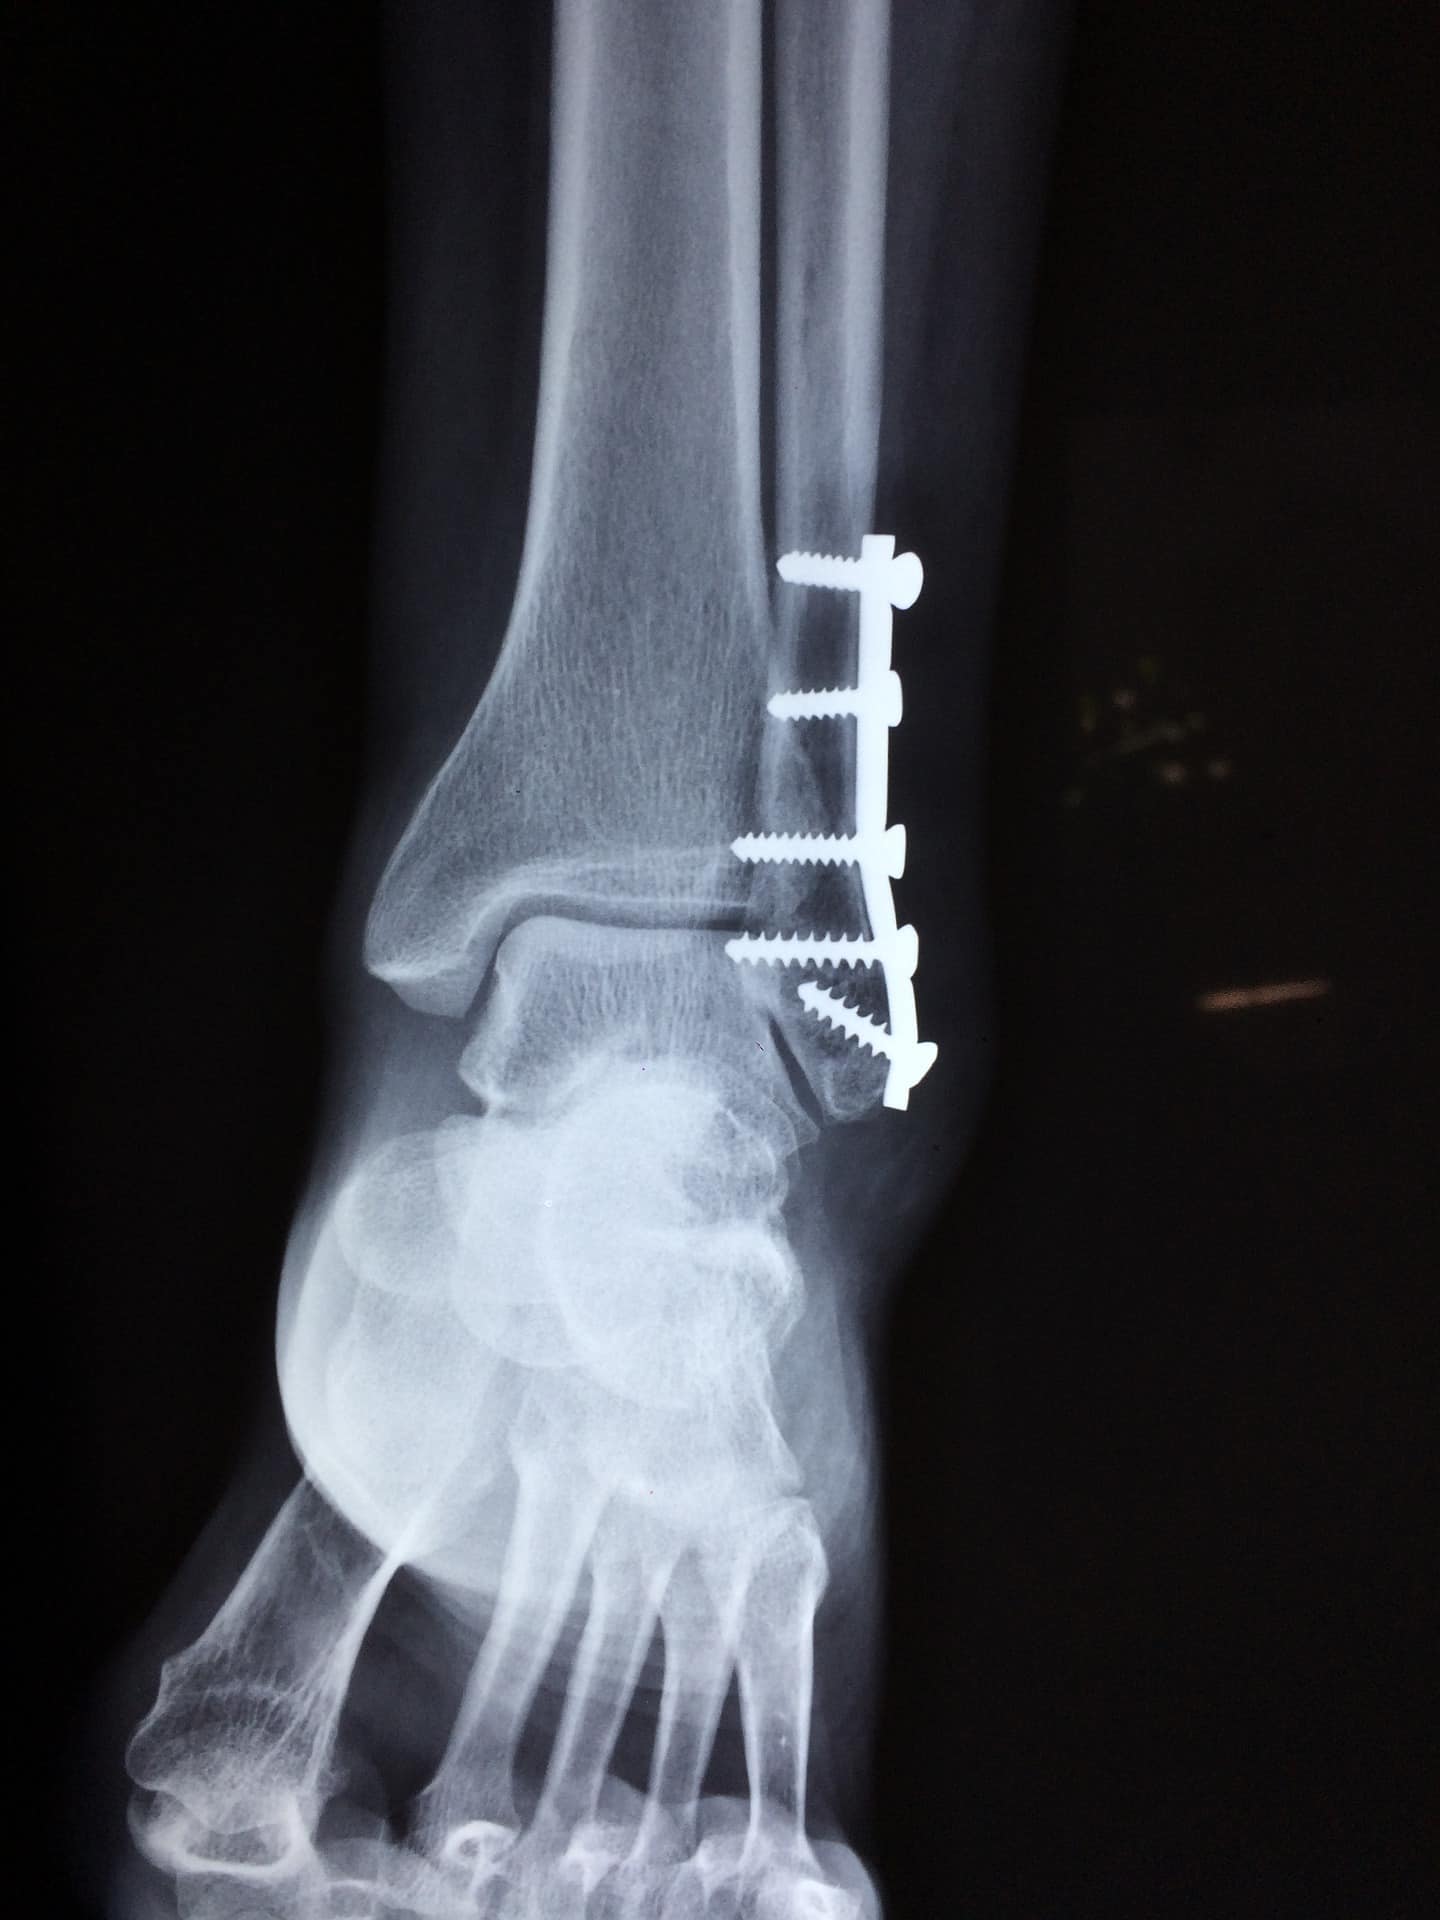

En cas de suspicion ou de douleur, il est crucial de se faire diagnostiquer par un spécialiste. Le diagnostic de l’hallux valgus est simple : un examen clinique à l’œil nu suffit. Une radiographie est cependant nécessaire pour évaluer le degré de déviation de l’orteil.Il faut donc bien choisir ses chaussures en évitant les modèles avec des avant-pieds serrés (bouts pointus) :